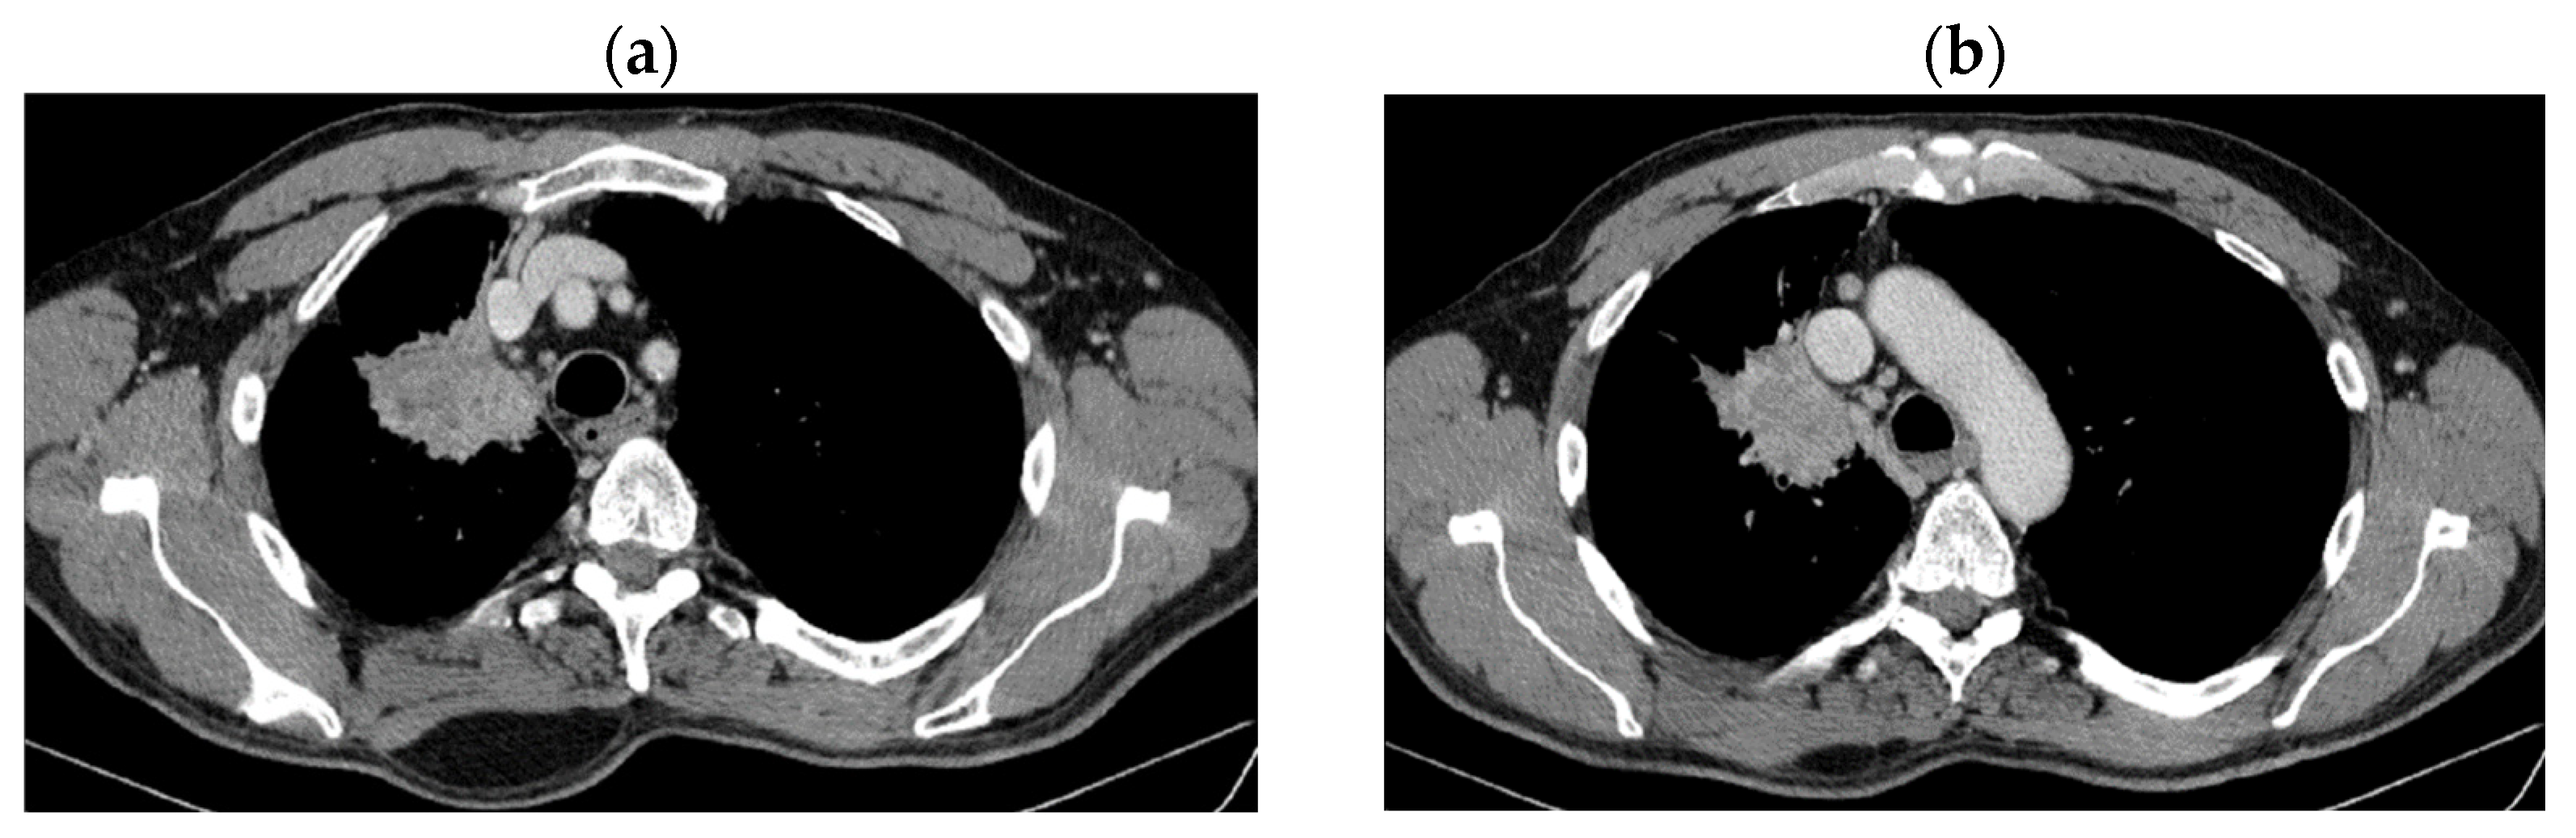

2. Case Presentation

2.1. Systemic Third-Line Therapy (4xDocetaxel) Was Initiated 04–07/2020

2.2. Monitoring 2022: Oncological Commission 1910/16.08.2022

2.3. Oncological Committee 07/25/2023 Recommended